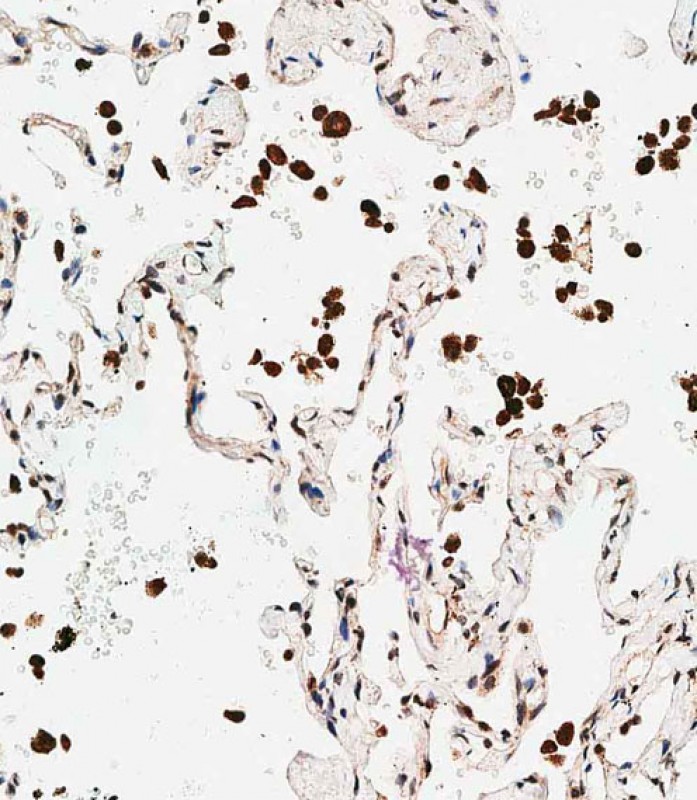

分类: 科研抗体货号: P34691别名: Triggering receptor expressed on myeloid cells 2, TREM-2, Triggering receptor expressed on monocytes 2, Trem2, Trem2a, Trem2b, Trem2c应用: WB,IHC反应种属: Mouse